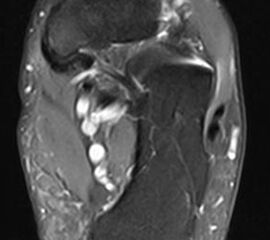

Abbildung 2.3.

Klärung bei Schmerzen im rechten OSG bei OCL an der medialen Talusschulter. Z. n. OSG-Distorsion vor 2 Jahren und Z. n. OSG-Fraktur / Syndesomosenruptur. Ausgedehnte OCL, hier jedoch kein erhöhter Knochenmetabolismus; lediglich Nachweis einer Stressreaktion im Bereich der Synchondrose eines Os trigonum als Schmerzursache.

Zum Lesen der Bildbeschreibung und zur Vollansicht bitte das Bild anklicken. Bild: H. C. Rischke